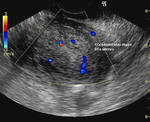

Ultrasound images of carcinoma of endometrium

Transabdominal and transvaginal sonography of the uterus in this postmenopausal patient reveals: 1) Grossly thickened endometrium 2) fine cystic lesions within the endometrial mass 3) invasion of the myometrium by the mass 4) increased vascularity of the lesion on color doppler imaging. These ultrasound images suggest Stage 1B (FIGO) carcinoma of the endometrium. The patient underwent hysterectomy after histopathological study confirmed the presence of malignancy (adenocarcinoma).